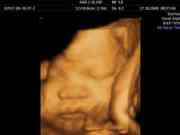

四维彩超[1]是大部分医生都会建议孕妇检查的项目,但是通常情况下孕妇是不知道四维可以检查的项目有哪些的,也不知道可不可以不做这个项目,其实四维彩超检查还是很有必要的,他除了可以检查胎儿的面部发育、脊椎发育、神经系统发育以外还可以让孕妇多方位的看到胎儿,还可以纪录影片,给胎儿做一个成长记录,是很好的一个项目。

四维彩超主要检查的是胎儿的面部发育、脊椎发育、神经系统发育、消化系统发育以及泌尿系统发育的发育情况,查看是否有异常,下面进行说明:[2]

四维彩超可以清晰显示胎儿的面部发育情况,实时显示出胎儿是否有着面部畸形的情况。